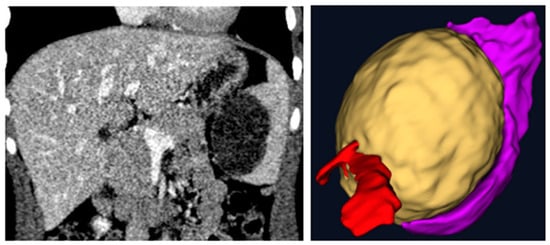

- Patient 2: affected by a splenic cyst of 6 cm, 16 years old, 82 kg, no other comorbidity.